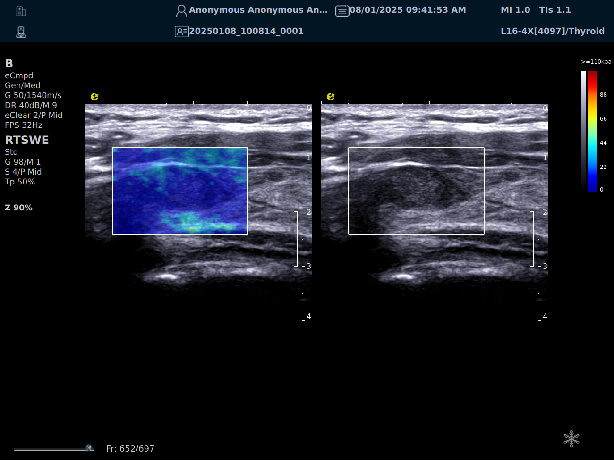

实时剪切波弹性成像

评估组织的软硬,并且提供定量数值,从而提示组织的良恶性。

鉴别诊断、精准分级、定量评价、穿刺引导、疗效评估、随访观察

image.png

恶性占位常常向周边组织进行侵润及扩散,二维很难观察到浸润部分的边界。使用实时剪切波成像能够对占位及周边组织进行硬度评估,通过颜色编码来区分不同组织的硬度信息,直观的观察占位组织的边界信息,更方便区分占位组织和正常组织的边界,准确评估消融范围。